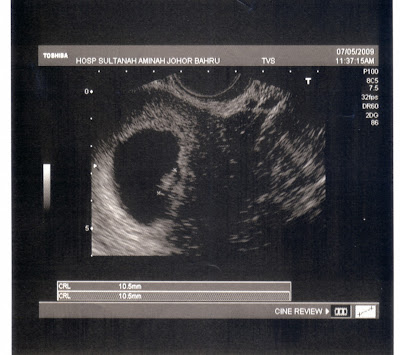

Heartbeat

ni scan just nampak sac jek, lom tau brape week